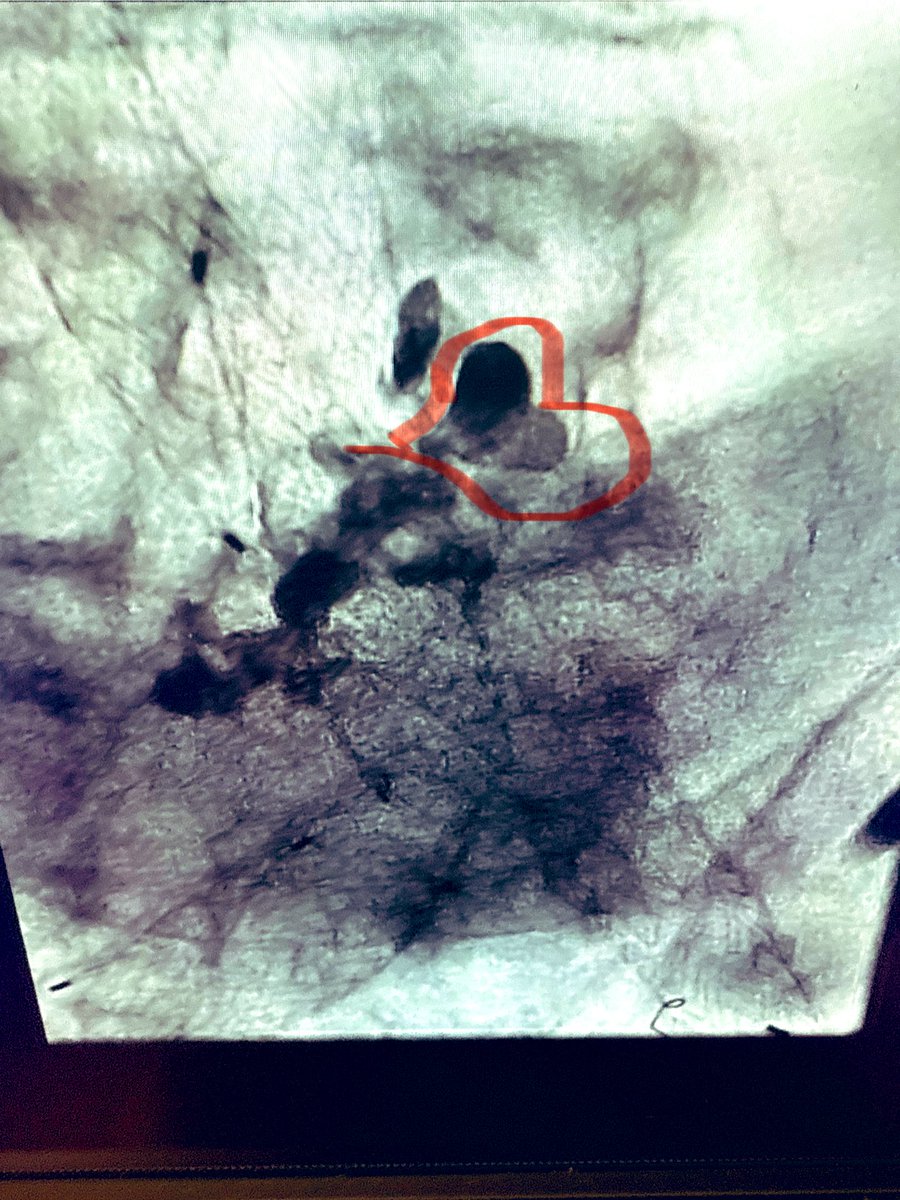

استشاري قسطرة الاوعية الدموية والاشعة التداخلية ,مهتم بعلاج الدوالي وتليفات الارحام واعادة التروية للشرايين الطرفية.